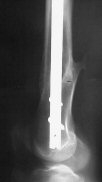

1. Percutaneous nailing is truly minimally invasive technique, but, unfortunately, nails are not reliable in many hands.

Attached are few examples from our Hospital:

B. Fixation loosening: distal cutting of the nail, non-unions do happen (cases attached).

Locking Plating has more distal screws than any nail, fixed angles and provides much better fixation, especially in osteoporotic bone.